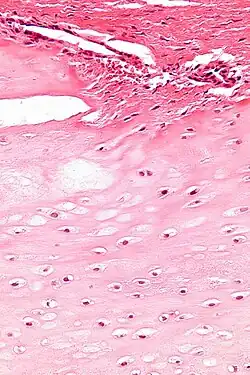

| Micrograph of an enchondroma. H&E stain. |